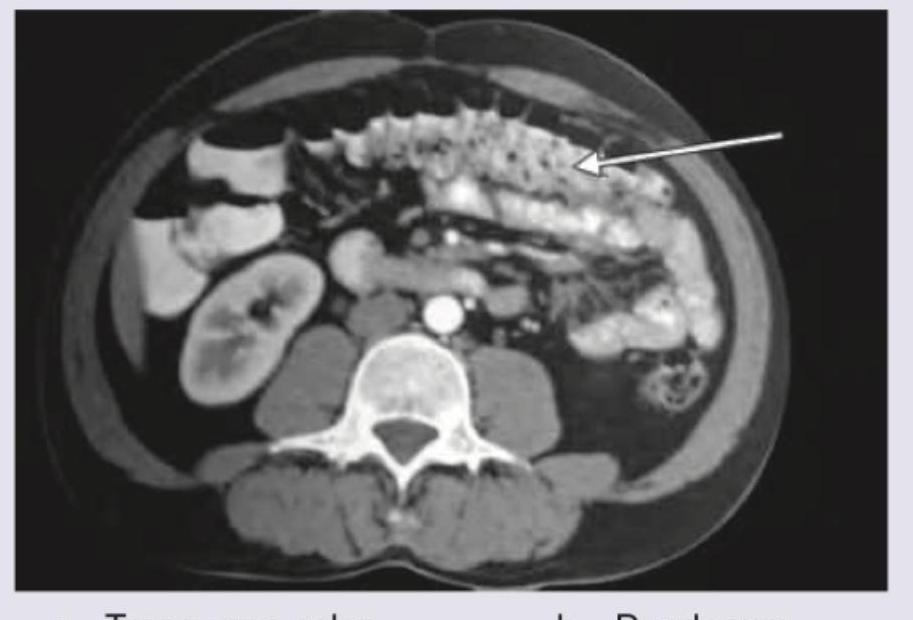

The structure marked by arrow in CT abdomen:

Explanation: ***Correct Answer: Duodenum*** - The arrow points to a C-shaped structure located in the **retroperitoneum**, anterior to the right kidney and vertebral body, consistent with the location and appearance of the **duodenum** on axial CT - The characteristic **thickened, enhancing wall** and mucosal folds further distinguish the duodenum - The duodenum is a retroperitoneal structure that wraps around the head of the pancreas in a C-shaped configuration *Incorrect: Transverse colon* - The transverse colon is typically located more anteriorly in the abdomen and often contains **feces** and **intraluminal gas**, which are not seen in the indicated structure - It has a larger caliber and generally a different mucosal pattern than the structure pointed to by the arrow - The transverse colon is an intraperitoneal structure, not retroperitoneal *Incorrect: Superior mesenteric vein* - The superior mesenteric vein is a **vascular structure** located in the mesentery, typically seen anterior to the aorta and to the right of the superior mesenteric artery - It appears as a **round, enhancing vessel filled with contrast media**, which is distinct from the C-shaped, bowel-like structure marked by the arrow - Would not show mucosal folds or bowel wall characteristics *Incorrect: IVC* - The IVC (Inferior Vena Cava) is a large **retroperitoneal vein** situated to the right of the aorta and posterior to the head of the pancreas and duodenum - It would appear as a **large, circular or oval contrast-filled vessel**, much larger than the structure indicated by the arrow and in a more posterior location - The IVC does not have the C-shaped configuration or mucosal characteristics of the marked structure